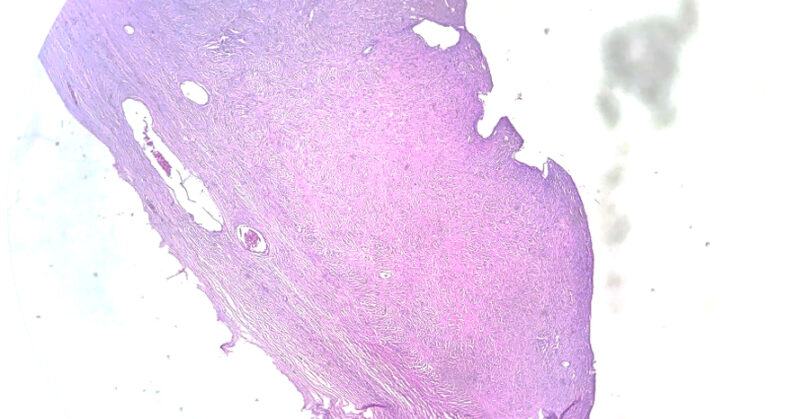

Macroscópicamente, los tumores mejor diferenciados consisten en masas quísticas, generalmente de una sola cavidad que contienen líquido claro o viscoso.

Puede haber proyecciones papilares, la mayoría sobresalen hacia la cavidad, pero pueden aparecer en la superficie exterior de la tumoración.

Microscópicamente, se observa un revestimiento de células cuboides a columnares que recubren los quistes y las papilas, aunque hay un amplio espectro morfológico donde el revestimiento es de una sola capa de células aplanadas, sin atipia, complejidad arquitectural ni invasión.

En este caso por su patrón de crecimiento quístico más proyecciones papilares, tipo de células encontradas y por la ausencia de atipia e invasión, se denomina Cistadenoma seroso papilar de ovario.